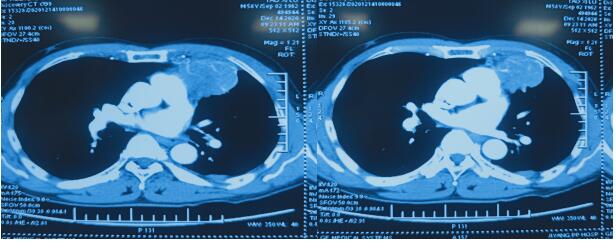

→术后3个月恢复情况

日前,区人民医院血液内科为一名肺癌患者成功实施了微创介入治疗,控制了病情。4月5日,患者陶某来院复查,进行第四次化疗,胸部肿瘤较前体积明显缩小。

患者陶某,2020年12月13日因胸痛来我院就诊,门诊给予胸部CT检查显示左肺上叶肿瘤并左肺内转移,之后住入血液内科,入院完善检查后行CT引导下肺肿瘤穿刺活检,术后病理示:左肺鳞癌,刘金峰主任根据患者情况给予综合评估,考虑患者胸痛明显,结合最新治疗指南后于2020年12月25日行左肺癌碘125粒子置入术,手术顺利,术后恢复好。术后10余天胸痛就明显好转。为进一步巩固治疗,之后再次给予全身化疗4周期。患者目前胸痛消失,胸部肿瘤较前体积明显缩小。